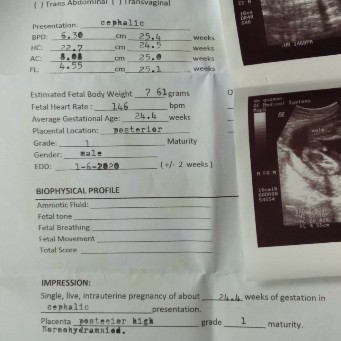

Ask ko lng po kung ok na po sa 6month ang haba ni baby at laki ng ulo .tas ok po b n nka pwesto na sya